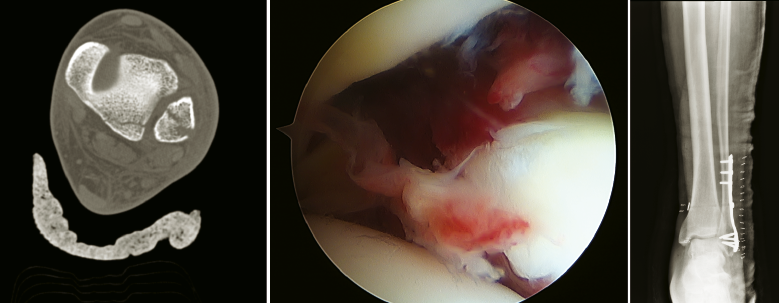

Figura 7. Artrodesis subastragalina artroscópica.

Figura 8. Fractura tobillo SER III. Asistencia artroscópica para valoración de sindesmosis.